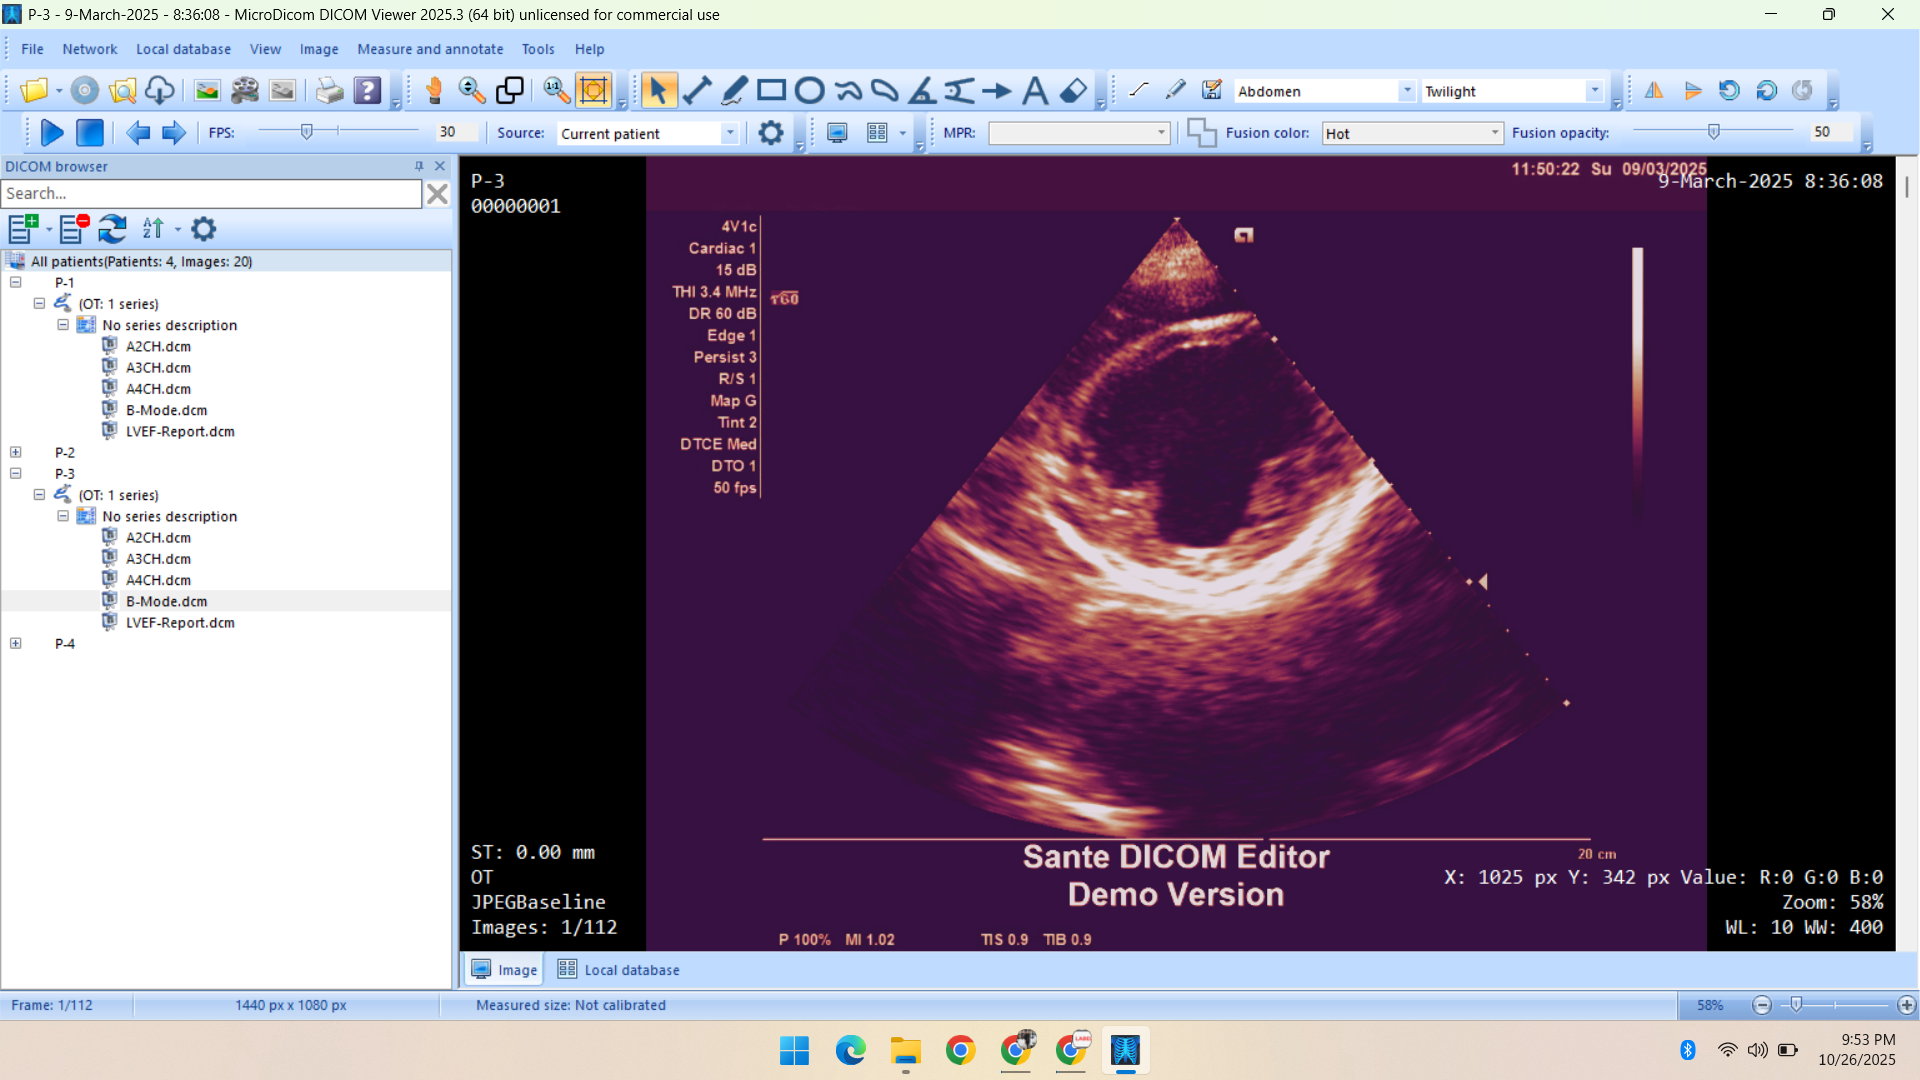

- Radiology Data – CT Scans, X-Rays, MRI, Echocardiography, Ultrasound.

Deep specialization in radiology, pathology, and histopathology datasets, annotated with medical precision.

Healthcare & Medical Data Supply

We specialize in healthcare datasets including radiology (CT, X-ray, MRI, Ultrasound, Echocardiography), pathology microscopy, and histopathology images — all ethically sourced and research-ready.

- Echocardiography